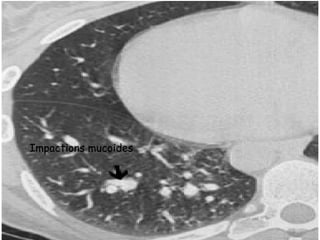

 TDM thoracique :

   Examen de référence pour mev des DDB proximales

(critère majeur de Dic) et des impactions mucoides .

   Permet de voir les images associées : infiltrats

labiles, atélectasies, aspect d’emphysème.

   Plus sensible et plus précoce pour Dic des fibroses

pulmonaires.

Bronchectasies centrales

Impactions mucoides